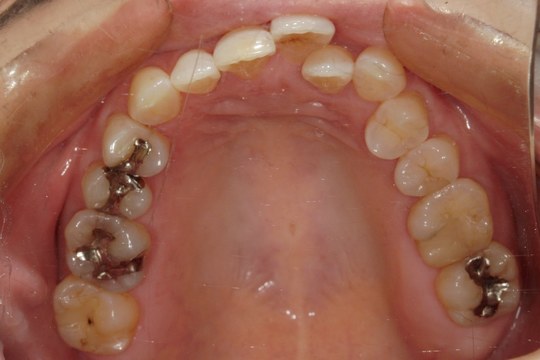

After

浜松市中央区・自動車学校前駅のインビザラインの症例

Y.S. 30代男性

全体的にガタガタしているのが気になるという主訴だったため、上下左右第一小臼歯を抜歯し、叢生を並べました。

治療の期間:R3. 9/1〜R5. 10/31

治療の価格:88万円